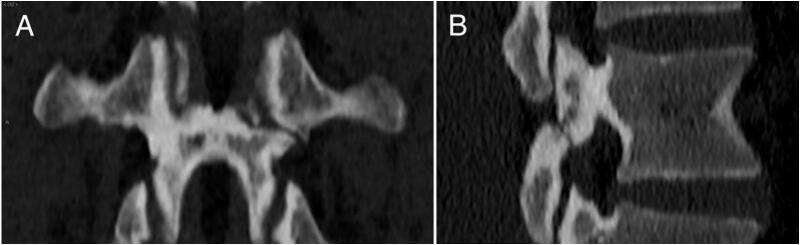

A 24-year-old male, following a sports-related trauma, developed persistent lower back pain. Imaging revealed a right L3 pedicle stress fracture with left lamina and pars interarticularis interruption. A minimally invasive percutaneous approach targeting the pedicle fracture was chosen. The procedure aimed to alleviate pain and promote non-union healing, without addressing the contralateral defect. The patient quickly recovered, achieving significant pain relief, and starting a tailored physical therapy program. At the 4-month follow-up, the pedicle fracture healed with callus formation. The patient returned to sports practice.

一名24岁男性,在一次与运动相关的创伤后,出现了持续性下腰痛。影像学检查显示右侧L3椎弓根应力性骨折,伴有左侧椎板和关节突峡部中断。选择了针对椎弓根骨折的微创经皮入路。该手术旨在缓解疼痛并促进骨不连愈合,而不处理对侧缺损。患者恢复迅速,疼痛明显缓解,并开始了量身定制的物理治疗计划。在4个月的随访中,椎弓根骨折愈合,有骨痂形成。患者恢复了体育活动。